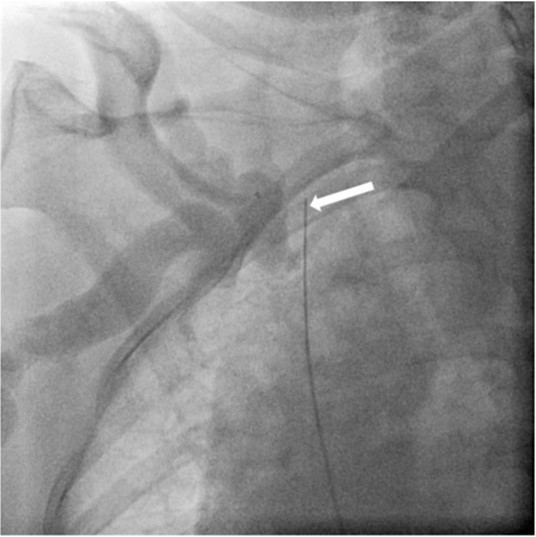

Fig. 4.

Fig 4. Fluoroscopic image shows Colapinto needle punctured the right superior vena cava across the obstructed segment. The tip of the needle is facing back side of the body (long arrow). Confined contrast leakage is noted around the obstructed right brachiocephalic vein (small arrows).

초음파 유도 하에 우측 팔의 동정맥루 graft를 천자한 후 정맥조영술을 시행하여 우측 상완두정맥의 폐색을 확인함(Fig. 1). 5Fr Cobra 카테터(Cook, Bloomington, IN, USA)와 친수성 0.035 inch 유도철사(Terumo, Tokyo, Japan)로 폐색부위의 통과를 시도하였으나 실패함. 우측 대퇴정맥을 천자하고9Fr 65cm sheath (Arrow, Deutschland, Erding, Germany)를 상대정맥까지 진입시킨 후 5Fr Davis 카테터를 통해 약 2cm 길이의 상완두정맥 폐색 부위를 확인함(Fig. 2). Davis 카테터와유도철사로 상대정맥에서 우측 상완두정맥으로 통과를 시도함. 유도철사의 soft tip 부분으로 시도하였을 때 통과가 되지 않아서 반대쪽 hard tip 부분으로도 통과를 시도 하였으나 실패함(Fig.3). 유도 철사의 soft tip 과 hard tip 양쪽 모두 사용 하여 통과를 시도하였으나 막힌 부위의 위쪽 부분은 앞쪽(anterior side of the body) 을 향하고 있고 아래쪽 부분은 뒤쪽(posterior side of the body)를 향하고 있어서 천자 방향을 맞추기 어려웠음(Fig. 3). 우측 내경정맥을 천자하고 5Fr sheath를 삽입함. Sheath를 통해서 5FrKumpe 카테터와 0.035 inch 유도철사로 위에서 아래 방향으로 폐색부위 통과를 시도함. Hard tip으로 시술 도중 폐색혈관 주위로 유도 철사가 천자되어서 조영제의 누출이 있었으나 천자부위 주에 국한되어 있었고 임상적으로 문제 있는 혈류역학적 변화는 오지 않았음. Kumpe 카테터와 유도철사로는 천자 방향을 맞추기가 어려워서TIPS set (Cook, Bjaeverskov, Denmark)를 사용하기로 함. 천자된내 경정맥에 10Fr introducer sheath를 삽입하고 20G Colapinto needle을 폐색부위까지 진입시킴. 양쪽에서 정맥 조영술을 시행하여 폐색된 부위의 위치와 길이를 여러 각도에서 정확히 파악한 후, 폐색 부위를 천자함(Fig. 4). 천자 후 Colapinto needle을 통해 유도철사를 상대정맥에 진입시킴. 대퇴동맥을 통하여 삽입된 snare 카테터(ev3, Plymouth, MA, USA)를 이용하여 대퇴정맥 밖으로 유도철사를 빼냄(through and through technique)(Fig 5). 유도 철사만 통과된 상태에서 천자부 주위에 여러번의 천자로 인한 조영제 누출이 있었으나 주출된 조영제의 양이 적었으며 천자부 주위에 국한되어 있었음. Tractogram시행시 조영제의 누출은 보이지 않아서 유도 철사 주위에 국한 되어 있어서 풍선확장술을 시행 하기로 함(Fig. 6).대퇴 정맥을 통해 유도철사를 0.035 inch Amplatz wire(Cook, Bjaeverskov, Denmark)로 교체하여 내경정맥까지 진입시킨 후 풍선카테터 (Bard, NJ, US)를 삽입함.천자된 통로를 따라 직경 6 mm에서부터 16 mm까지의 풍선카테터로 차례대로 풍선확장술을 시행함(Fig. 7). 시술 후 정맥조영술에서 폐색부위는 개통되어 원활한 혈류를 보였음(Fig. 8). 시술 후에 오른쪽 팔의 종창은 호전됨.